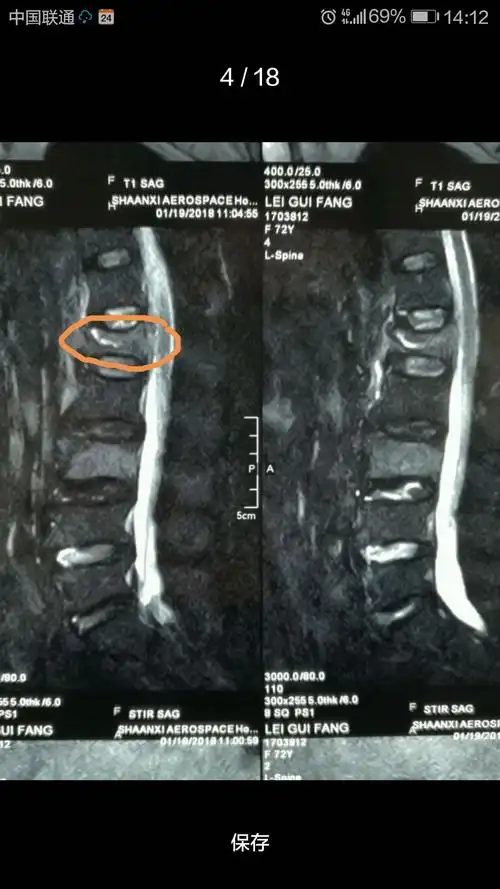

腰椎压缩性骨折新鲜原创

腰椎压缩性骨折新鲜